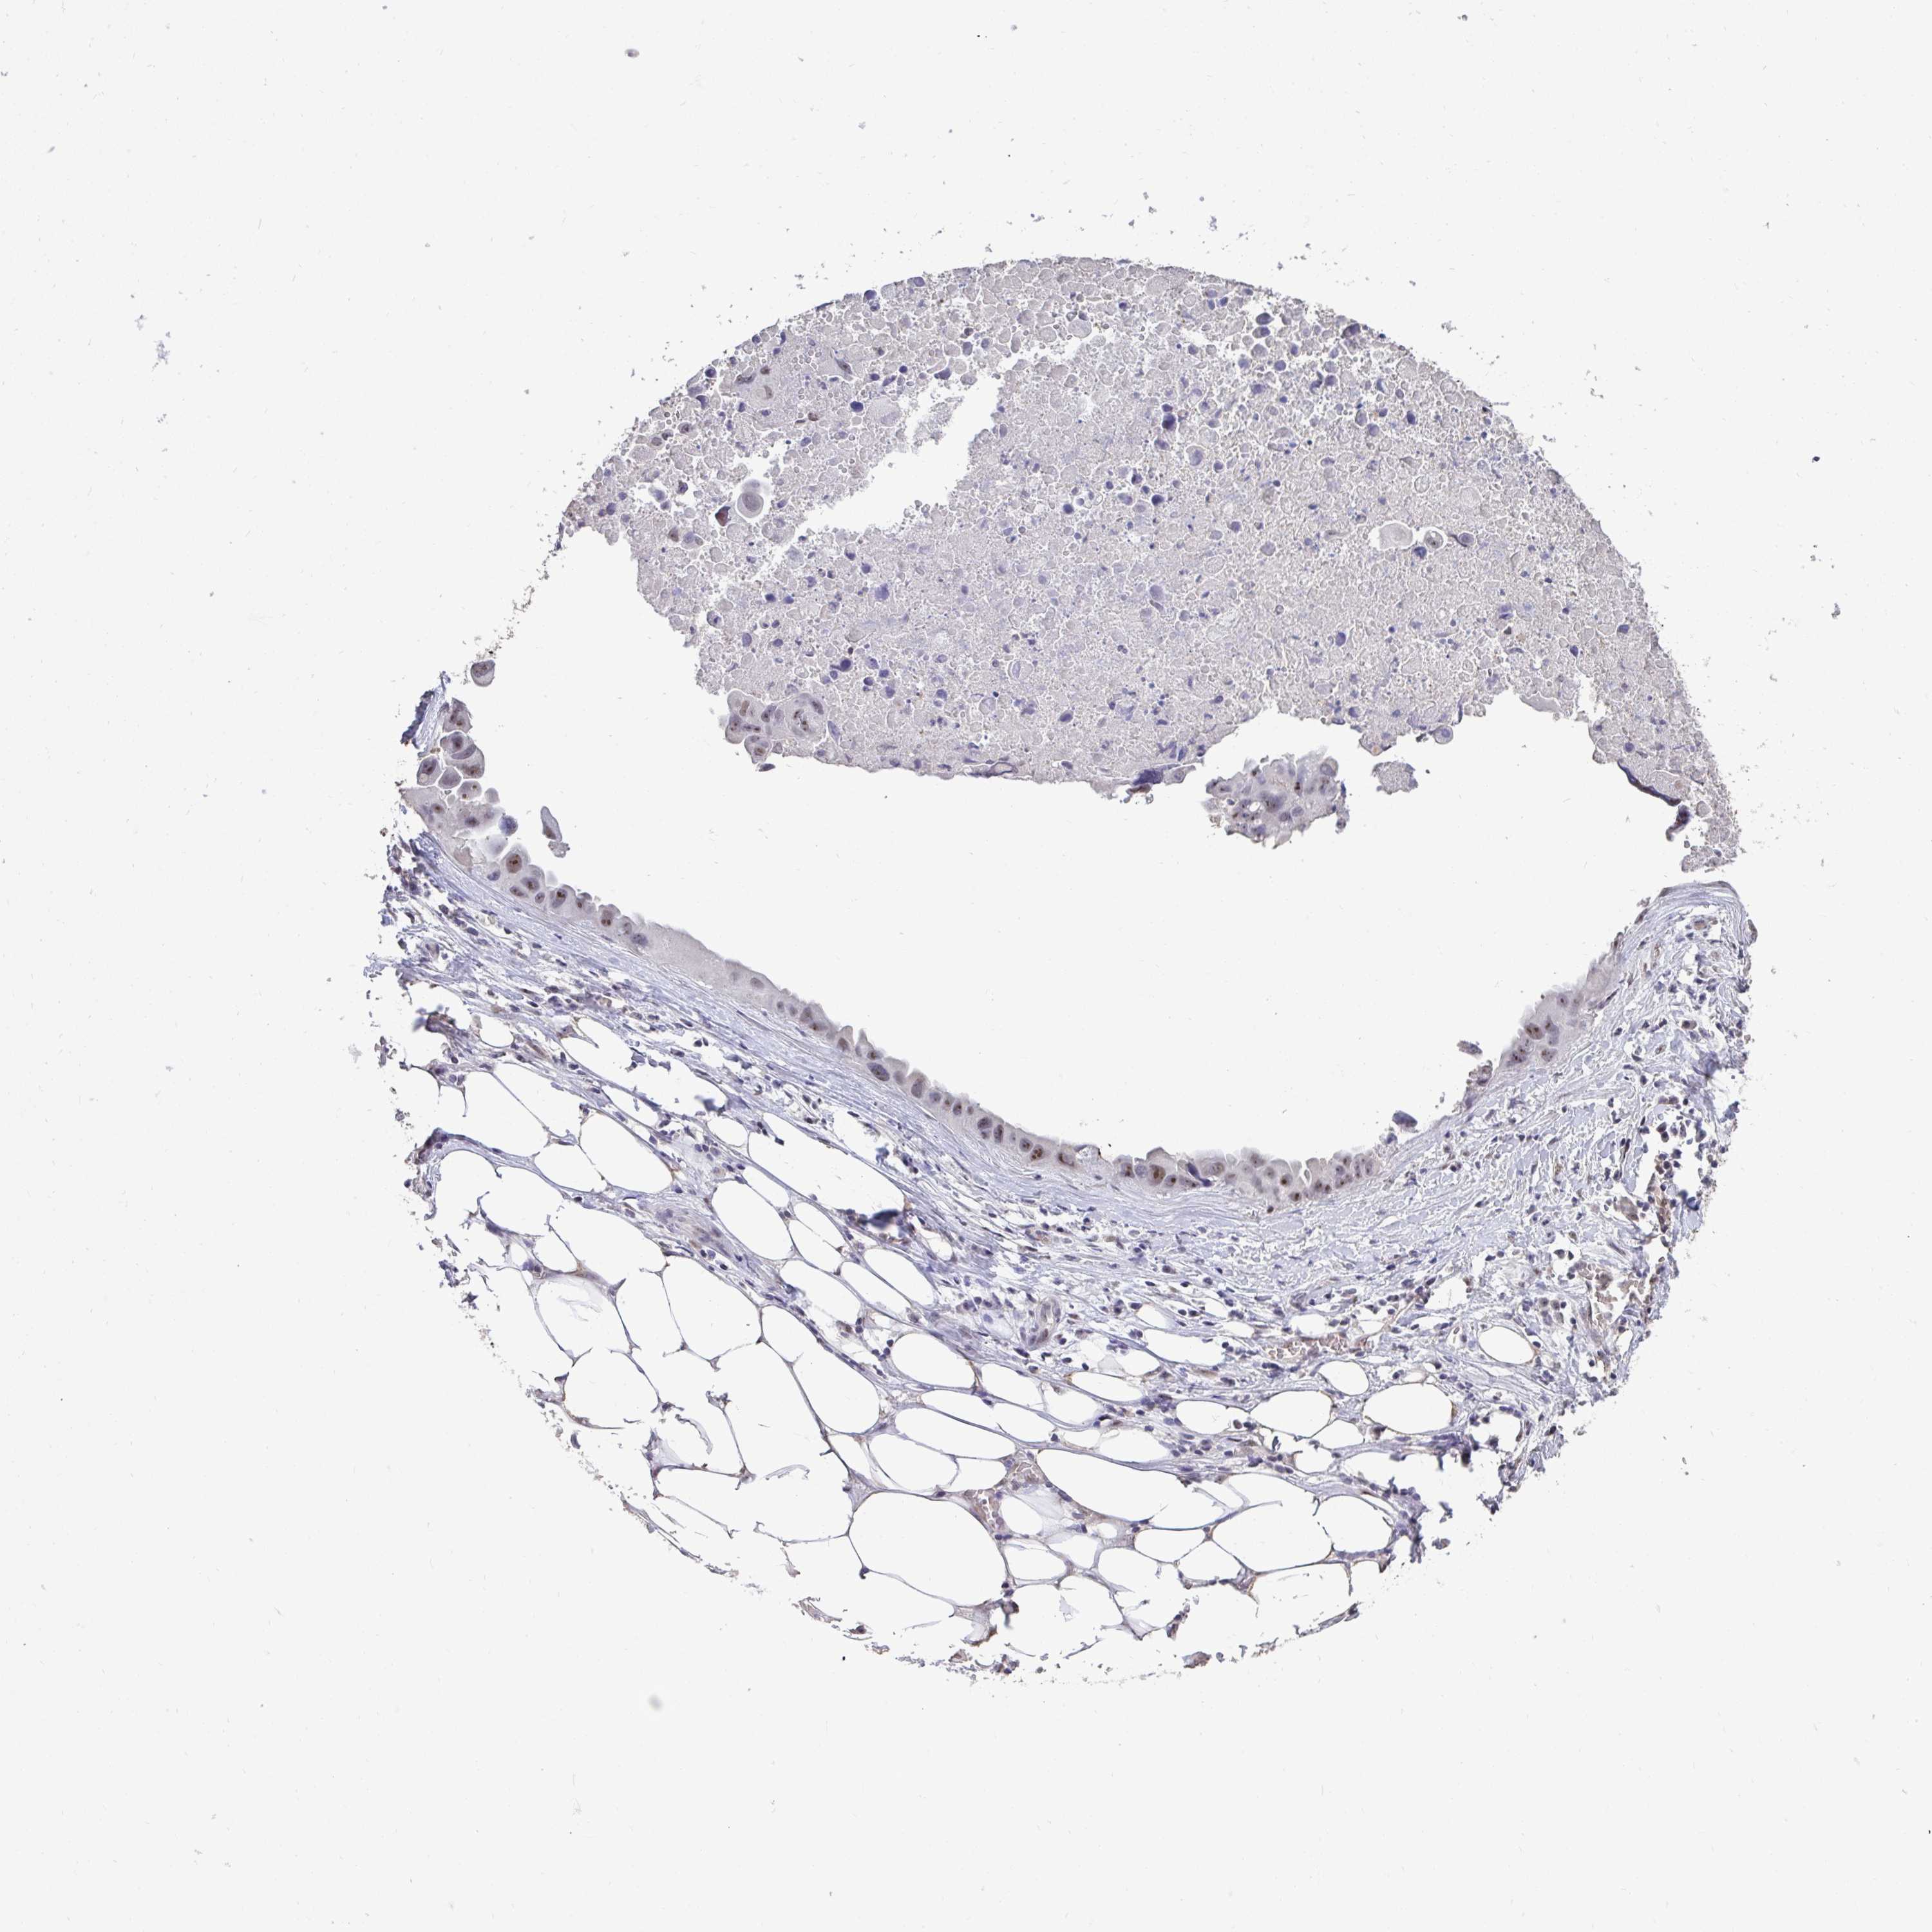

LUNG ADENOCARCINOMA (VALIDATION) - Interactive survival scatter ploti

The Survival Scatter plot shows the clinical status (i.e. dead or alive) for all individuals in the patient cohort, based on the same data that underlies the corresponding Kaplan-Meier plots. Patients that are alive at last time for follow-up are shown in blue and patients who have died during the study are shown in red.

The x-axis shows the expression levels (FPKM) of the investigated gene in the tumor tissue at the time of diagnosis. The y-axis shows the follow-up time after diagnosis (years). Both axes are complimented with kernel density curves demonstrating the data density over the axes. The top density plot shows the expression levels (FPKM) distribution among dead (red) and alive patients (blue). The right density plot shows the data density of the survived years of dead patients with high and low expression levels respectively, stratified using the cutoff indicated by the vertical dashed line through the Survival Scatter plot. This cutoff is automatically defined based on the FPKM cutoff that minimizes the p-score. The cutoff can be changed by dragging the vertical line or by entering a cutoff value in the square labeled "Current cut-off".

Under the Survival Scatter plot the p-score landscape (black curve; left axis) is shown together with dead median separation (red curve; right axis). Dead median separation is the difference in median mRNA expression between patients who have died with high and low expression, respectively. It is calculated as follows: median FPKM expression of dead patients with high expression - median FPKM expression of dead patients with low expression. This is intended to aid the user in visually exploring custom cutoffs and the associated p-scores and dead median separation.

Individual patient data is displayed and can be filtered by clicking on one or more of the category buttons on the top of the page. Categories describing expression level and patient information include: high, low, alive, dead, female, male and tumor stages. The scale of the x-axis can be toggled between linear and log-scale by clicking on the "x log" button. Mouse-over function shows TCGA ID, patient information and mRNA expression (FPKM) for each patient.

& Survival analysisi

Kaplan-Meier plots summarize results from analysis of correlation between mRNA expression level and patient survival. Patients were divided based on level of expression into one of the two groups "low" (under cut off) or "high" (over cut off). X-axis shows time for survival (years) and y-axis shows the probability of survival, where 1.0 corresponds to 100 percent.

SENP3 is not prognostic in Lung Adenocarcinoma (validation)

Best expression cut offi

Based on the FPKM value of each gene, patients were classified into two groups and association between prognosis (survival) and gene expression (FPKM) was examined. The best expression cut-off refers the FPKM value that yields maximal difference with regard to survival between the two groups at the lowest log-rank P-value. Best expression cut-off was selected based on survival analysis .

When clicking on this number, the vertical dashed line indicating cut-off, the interactive survival plot, and the Kaplan-Meier curve will be adjusted to show results based on the best expression cut-off.

: 36.4